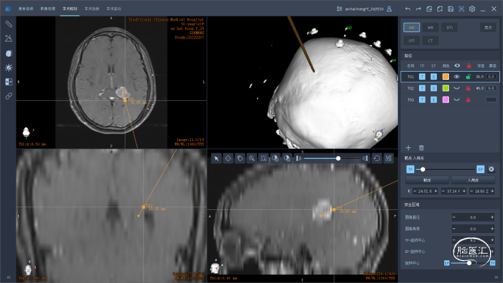

术前影像检查

头颅MRI

头颅MRI增强

左侧侧脑室三角区脑膜瘤。

收集MRI及定位CT数据,用睿米机器人进行数据融合,靶路径设计,完成术前计划。